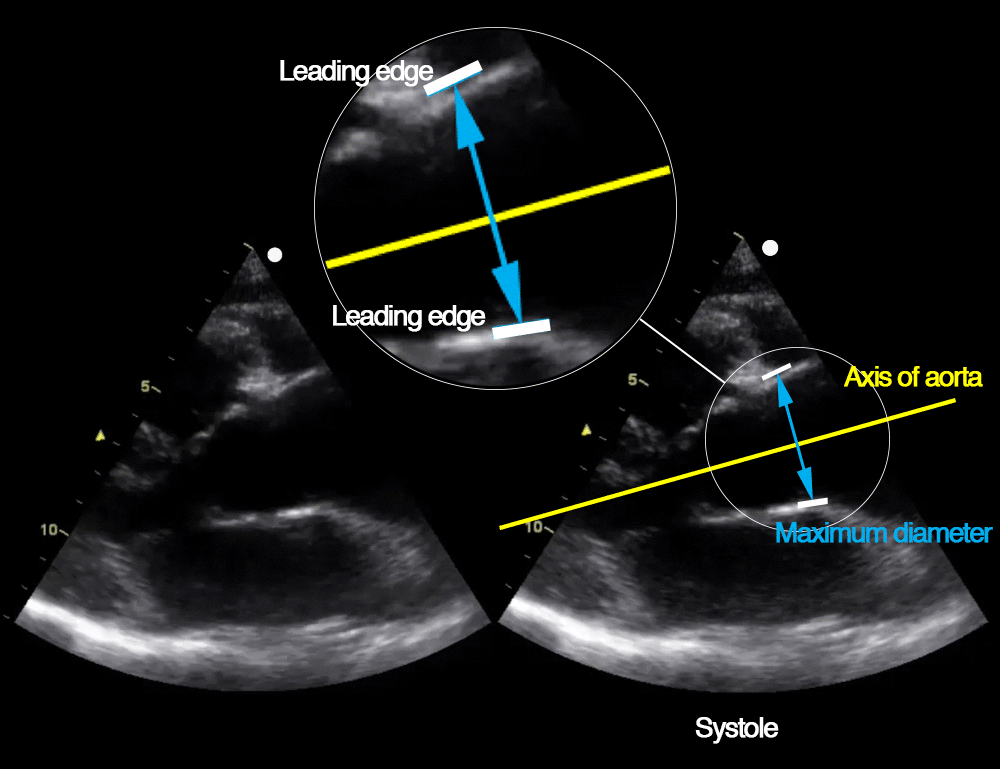

What Is Leading Edge To Leading Edge Echo . Aortic measurements should be taken (by. First, convention is essential for meaningful consistency. Mid right coronary cusp and the edge of the commissures between the lcc and ncc. “leading edge” connotes the edge of the aortic wall that is the closest to the probe (at the top of the inverted “v” of the ultrasound. By transesophageal echo (tee), the leading edges are the outer posterior wall and inner anterior wall. Second, the leading edge is the closest to the echo.

Aortic measurements should be taken (by. Mid right coronary cusp and the edge of the commissures between the lcc and ncc. By transesophageal echo (tee), the leading edges are the outer posterior wall and inner anterior wall. First, convention is essential for meaningful consistency. “leading edge” connotes the edge of the aortic wall that is the closest to the probe (at the top of the inverted “v” of the ultrasound. Second, the leading edge is the closest to the echo.